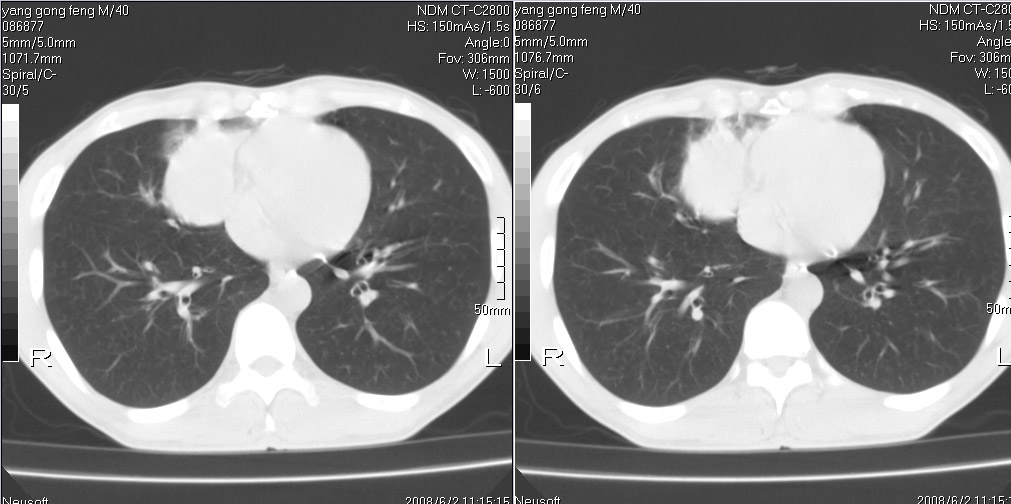

标题: CT15138:男,40,咳嗽胸痛. [打印本页]

标题: CT15138:男,40,咳嗽胸痛.

外院穿刺未见癌细泡,结核菌素实验阳性,未正规治疗2个月复查病灶及纵隔淋巴结增大

考虑周围型肺癌可能性大

考虑周围型肺癌可能性大!

考虑右肺中叶周围型肺癌并纵隔淋巴结转移。

考虑周围型肺癌伴纵膈淋巴结转移可能性大